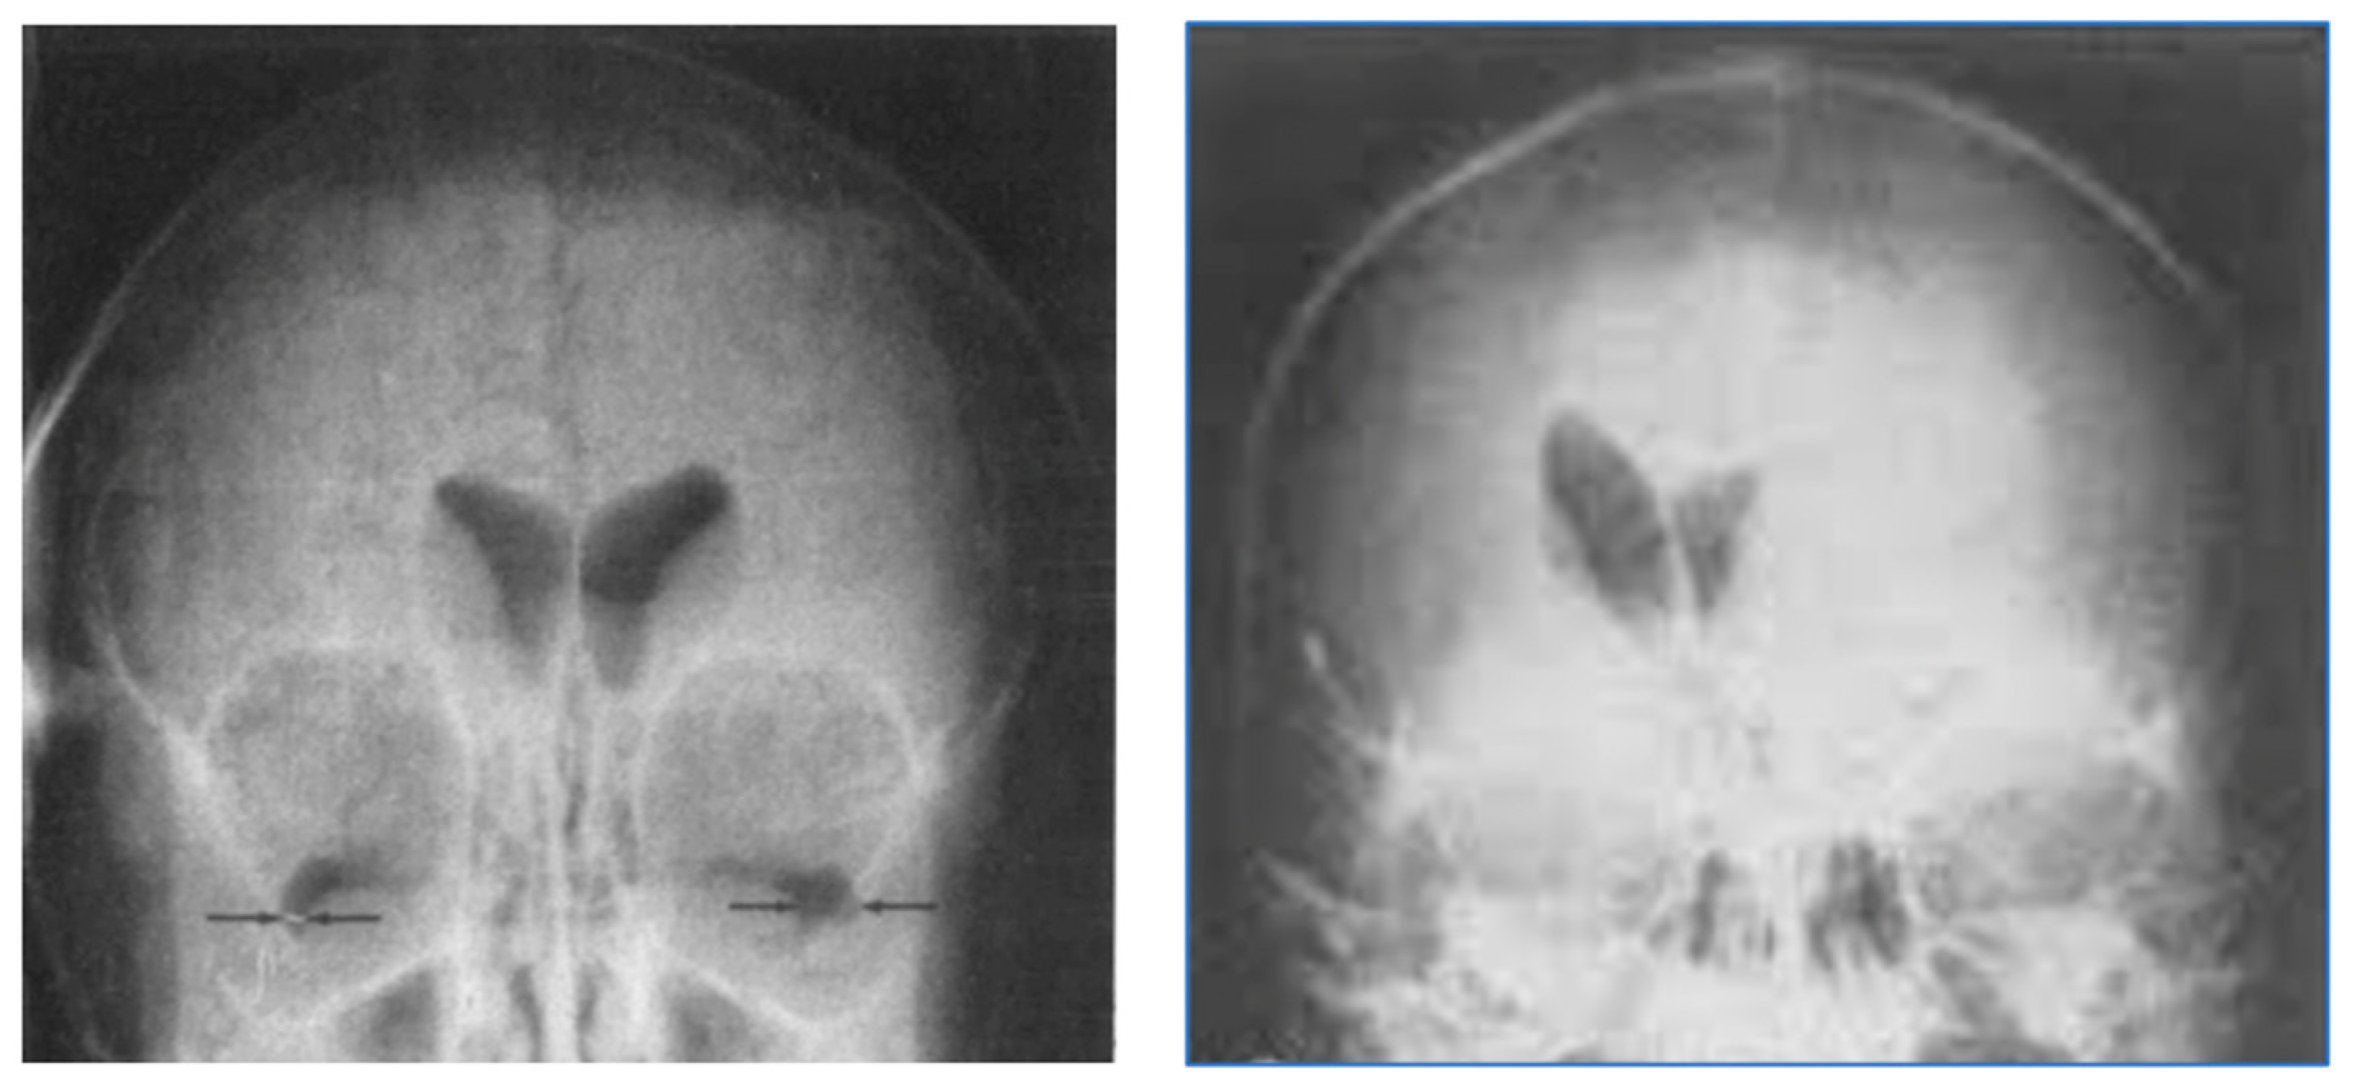

Figure 19 shows narrow mD dSIR images in the patient after one month’s abstinence (left column) and after nine months’ abstinence (right column). Extensive abnormal high signal is seen in white matter after one month’s abstinence (left column). There is marked reduction in the extent of these high signal abnormalities in white matter after nine months abstinence from whiteout sign grade 4 to grade 2 (right column). The patient clinically improved during this period.

Figure 19.

Case 1 patient with methamphetamine use disorder. Comparison of narrow mD dSIR images after one month’s abstinence (left column) and after nine months’ abstinence (right column). After one month’s abstinence the images show widespread abnormal areas of increased signal in white matter (left column). After nine months abstinence, the images show extensive dark low signal areas (right column) consistent with marked regression of his disease during the period between one and nine months’ abstinence from whiteout sign grade 4 (right column) to grade 2 (left column). The boundaries between white and gray matter as well as between CSF and white matter around the lateral ventricles become more obvious after regression of the whiteout sign.